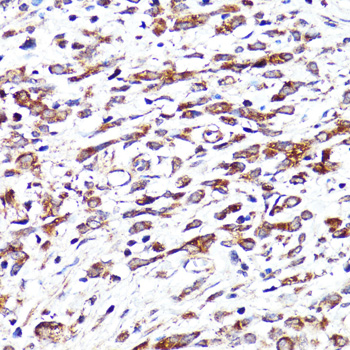

| Application: | WB IHC |

| Application: | WB IHC |

| Recommended Dilution: | WB 1:500 - 1:2000 IHC 1:50 - 1:100 |